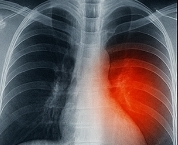

6. 폐암

기침이 수개월간 지속되면서 피 섞인 가래가 나오는 경우, 폐암 가능성을 의심해야 합니다. 특히 40세 이상 흡연자는 정기 검진이 필수입니다.

이런 경우 폐 CT, 흉부 엑스레이, 객담 검사, 폐기능 검사 등을 통해 진단을 진행합니다.